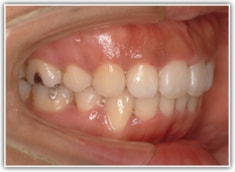

上顎前突ケース

治療法:表の矯正(T21ブラケット)

治療後(2年後)